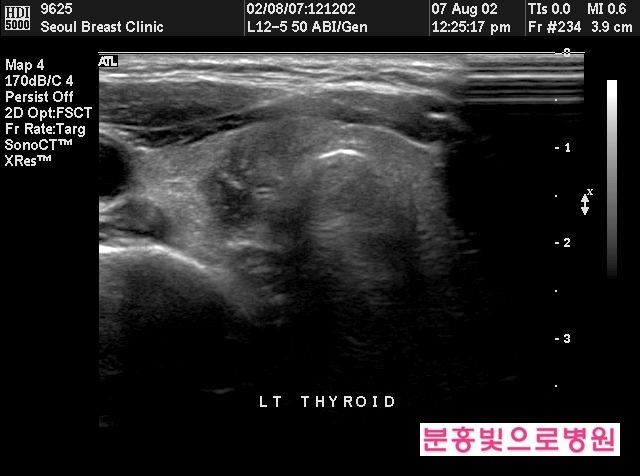

갑상선 초음파

촉진, 혈액 검사 등에 이상이 확실한 경우는 입상선 초음파 검사를 실시합니다.갑상선에 응어리나 결절, 종양의 유무를 관찰하고 병변의 형태와 크기, 범위를 알기 위해서는 갑상선 초음파는 반드시 필요합니다.고가의 MRI나 CT 대신 초음파 검사로도 수혹이나 갑상선염, 갑상선암 등을 진단할 수 있고 악성이 의심되면 세침 흡입으로 조직검사를 해야 합니다.조직검사 시 양성이라고 해도 초음파 결과가 좋지 않으면 경과를 지켜보면서 정기적인 검사를 해야 합니다.

갑상선 초음파는 단식 등 다른 준비가 없고 누운 상태에서 목에 탐촉자만 사용하기 때문에 크게 불편할 일이 없고 빨리 끝나기 때문에 검사가 어렵지 않습니다.단, 세침흡입생검은 항응고제를 복용 중인 경우 출혈이 발생할 수 있어 주치의와 상의 후 일정을 다시 잡아야 합니다.

갑상선 초음파는 갑상선 이상을 발견하고 평가하는 데 가장 정확한 방법이며 저렴하고 우수한 진단 도구입니다.메리제이 산부인과는 삼성서울병원 산부인과 전공의 및 정밀초음파 전임의, 청담마리 산부인과 원장을 역임하고 삼성서울병원 외래교수로 재직 중인 정경란 원장이 직접 진료합니다.